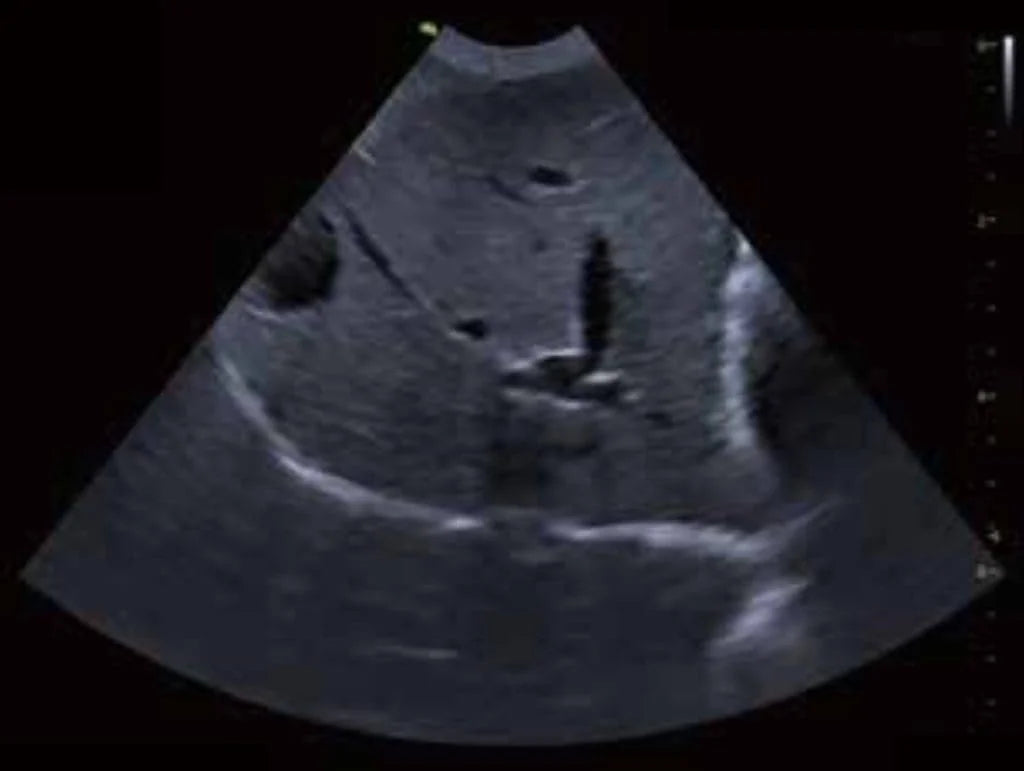

La ecografía abdominal se ha convertido en una herramienta esencial en la medicina veterinaria moderna. Es un examen no invasivo que permite a los médicos veterinarios observar en tiempo real los órganos y estructuras internas de los animales, ofreciendo una ventana precisa y detallada para el diagnóstico de una amplia variedad de patologías. La imagen que observamos aquí es un ejemplo de una evaluación ecográfica abdominal en la que se visualizan estructuras clave, permitiendo una evaluación detallada de la salud del paciente.

Este tipo de estudios permite a los veterinarios visualizar órganos como el hígado, los riñones, el bazo, el páncreas, la vejiga y los intestinos. A través de las imágenes ecográficas, los médicos pueden identificar cambios en la morfología de estos órganos, la presencia de líquido anormal en cavidades, tumores, cálculos y otros problemas internos que no serían detectables mediante un examen físico común. Algunos de los diagnósticos más comunes que se pueden realizar incluyen: